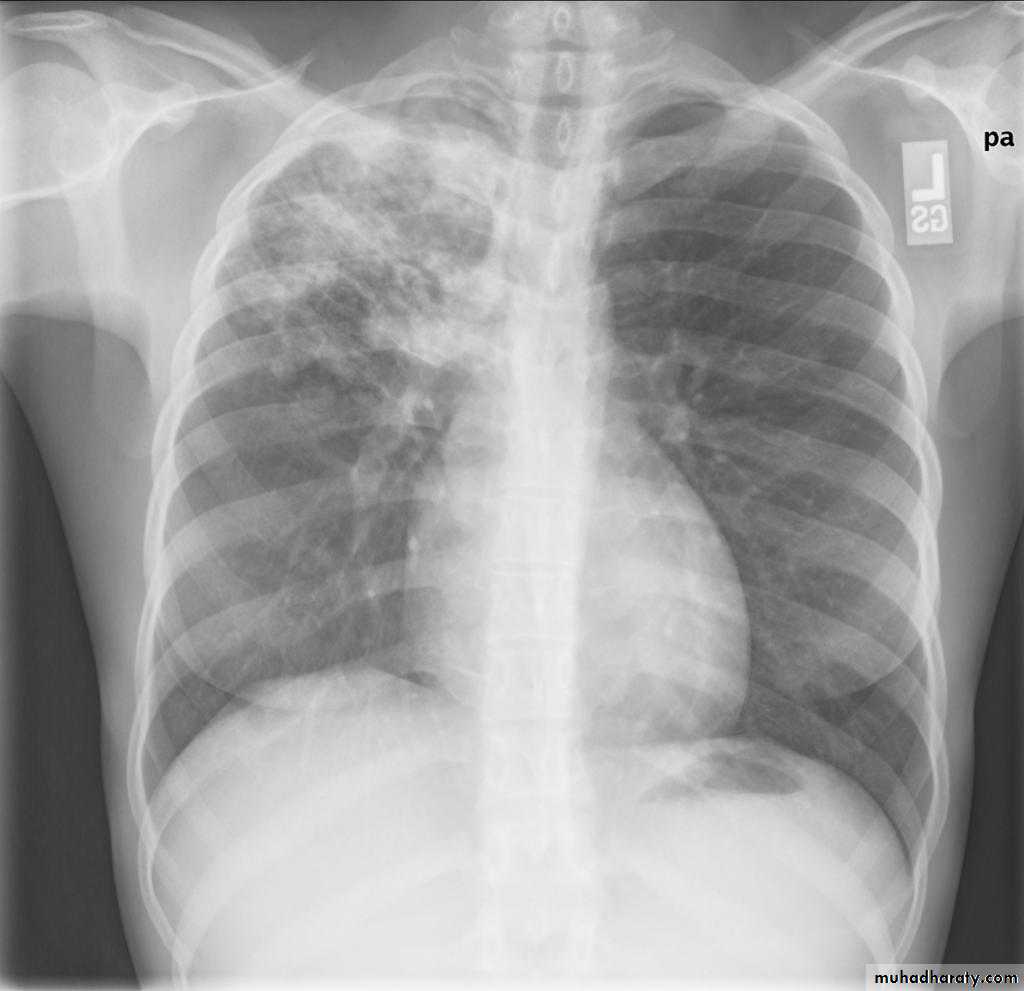

Right upper lobe consolidation

RUL consolidation will be seen as an increased opacity within the right upper lobe. Opacity may be sharply bordered by the horizontal fissureSome loss of outline of the upper right heart border may be apparent

Radiological sign in chest radiograph

Dense opacity seen above the horizontal fissure.

Air-bronchogram line

The lower border of the consolidation is sharply delinated by the horizontal fissure suggesting it lies in the anterior segment of the RUL